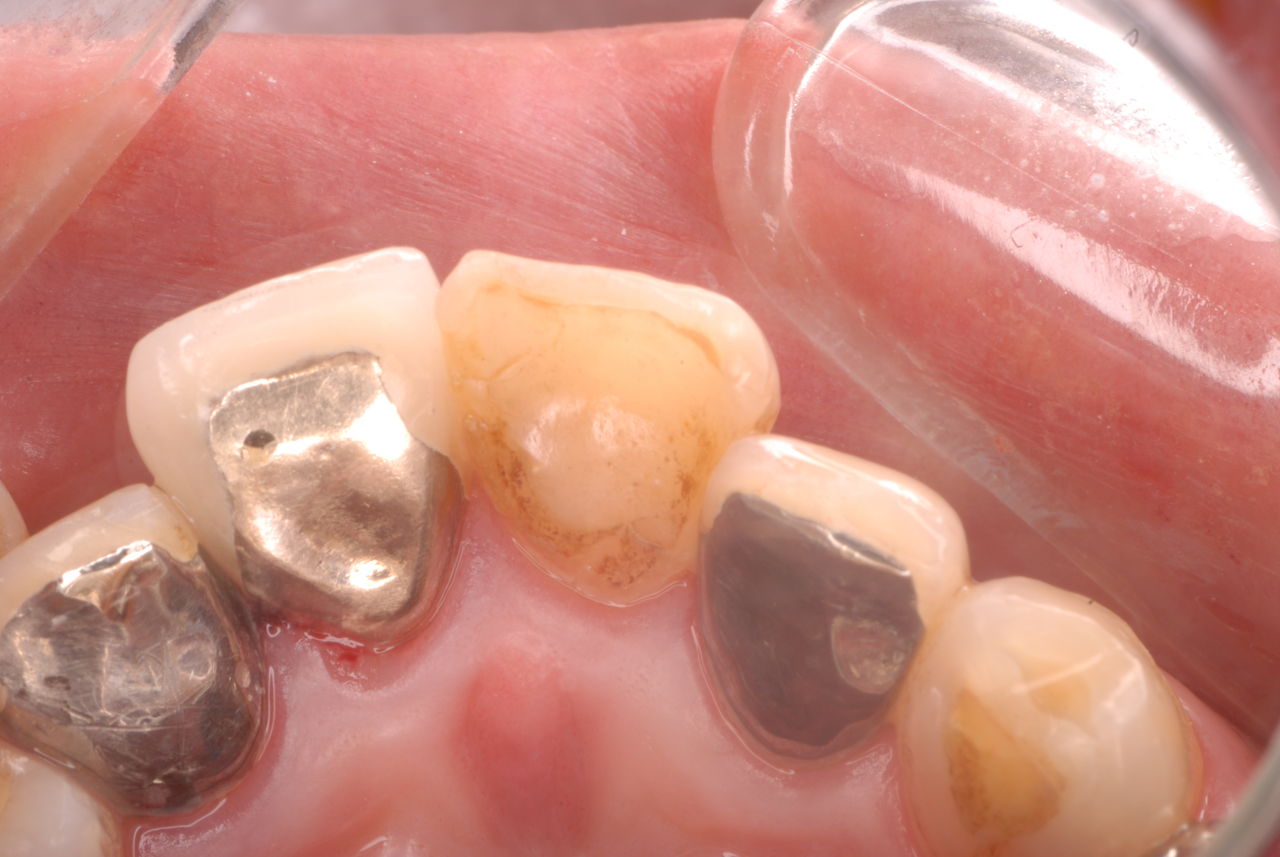

写真左下の親知らずが痛くなり抜歯しました。その後歯茎を除去して虫歯を露出させる処置を二回ほどしています。

レントゲンでは小さいですが、こう言う虫歯が一番怖いのです。

治療の成功率は極めて悪くすぐ再発しやすいのです。